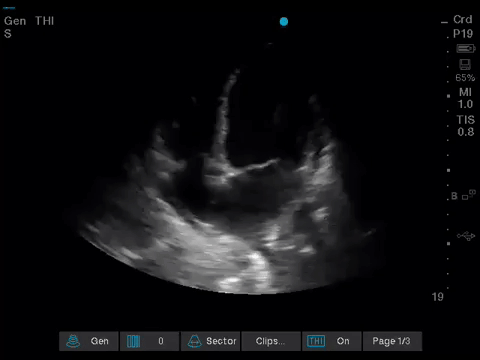

Before giving their clinical interpretation of the LUS findings, the POCUS team also scanned the heart and vasculature to obtain a more complete picture.

A comprehensive echocardiogram confirmed the POCUS findings. Her depressed LVEF was thought to be due to either septic cardiomyopathy or chemotherapy toxicity.